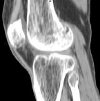

CT of the knee joint.